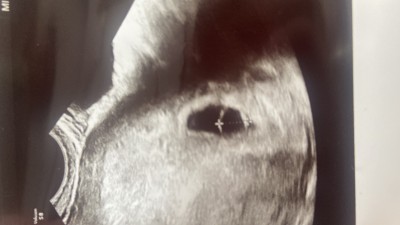

image Merhaba arkadaşlar  cuma günü kürtaj olacağım adet düzensizliğimden dolayı haftam hesaplanamadı 2 hafta önce 6 haftalık pazartesi gittiğimde tekrar 6 haftalık demişlerdi gelişmiyor hep geriden geliyormuş

kalp atışı yolk kesesi olunca duyulması gerekmiyor muydu

yolk kesesi sorunlu dedi bebek görünmüyormuş yol sac 6.69 anlayan varsa cevaplarsanız çok sevinirim

Gebelik haftası 6